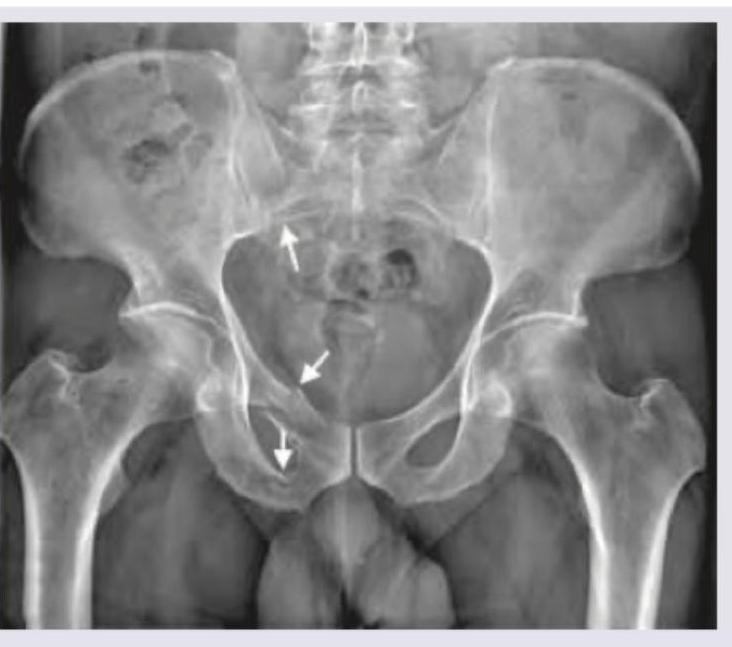

Explanation: ***Malgaigne fracture*** - This image demonstrates a **Malgaigne fracture**, characterized by **vertical sheer unstable pelvic fractures** involving the posterior pelvic arch (sacroiliac joint dislocation or sacral fracture) and two fractures of the ipsilateral anterior pelvic arch (pubic rami fractures). - The arrows in the image point to the fractures of the pubic rami and the displacement at the sacroiliac joint, consistent with the definition. *Straddle fracture* - A **straddle fracture** involves bilateral fractures of both the superior and inferior pubic rami, typically as a result of a direct blow to the perineum. - This image shows unilateral pubic rami fractures combined with a posterior injury (sacroiliac dislocation), which is characteristic of a Malgaigne fracture rather than a straddle fracture. *Pubic rami with penile fracture* - While there are pubic rami fractures visible, there is **no radiological evidence of a penile fracture** on an X-ray. Penile fractures are soft tissue injuries involving the tunica albuginea and are typically diagnosed clinically or with ultrasound/MRI. - The combination of anterior and posterior pelvic ring injuries observed in the image points to a Malgaigne fracture, which has a specific definition beyond just pubic rami fractures. *Sacroiliac joint dislocation only* - The image clearly shows disruption of the **sacroiliac joint** on one side, but it also demonstrates **associated fractures of the ipsilateral pubic rami**. - A diagnosis of "sacroiliac joint dislocation only" would be incomplete as it misses the critical anterior pelvic ring injuries, which together with the posterior injury define a Malgaigne fracture.

Explanation: ***Grade III*** - This image shows a **complete displaced fracture** of the femoral neck, but with the **distal fragment in valgus** position, which corresponds to Garden Grade III. - In Garden Grade III, the fracture is **complete and displaced**, but there is still some **engagement** of the fracture surfaces, leading to the valgus alignment of the head on the shaft. *Grade I* - Garden Grade I refers to an **incomplete impacted valgus fracture** of the femoral neck. - The fracture line is visible, but there is no displacement, and the head is tilted into a valgus position relative to the neck. *Grade II* - Garden Grade II describes a **complete but non-displaced fracture** of the femoral neck. - The fracture line extends across the entire neck, but the fragments remain in anatomical alignment without angulation or displacement. *Grade IV* - Garden Grade IV is characterized by a **complete and fully displaced fracture** of the femoral neck, with the **femoral head completely separated** from the shaft and in a neutral or varus position. - There is a complete loss of contact and alignment between the femoral head and the shaft, indicating significant instability.